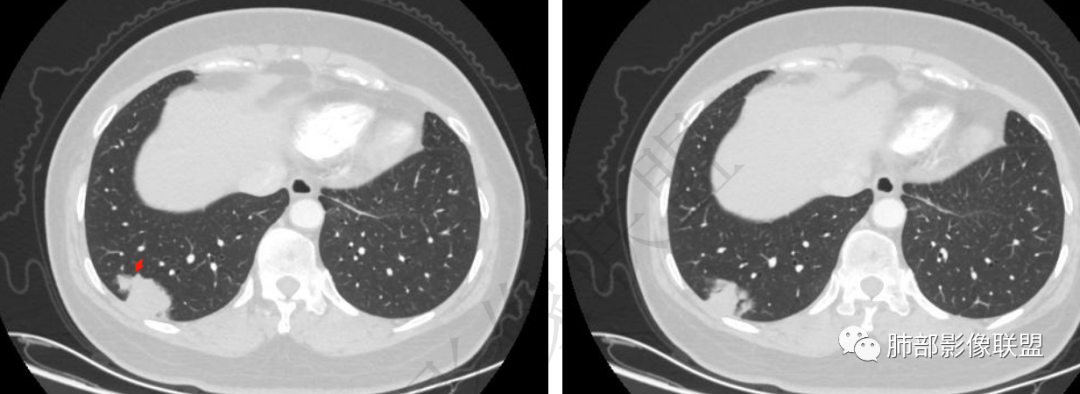

1.患者年龄不详,没有相关临床症状(体检发现)。

2.右肺下叶近胸壁处团片影,边界较清楚,表面欠规则,较均匀实行密度为主,边缘可见边界较清楚的磨玻璃密度区。相邻胸膜增厚,胸膜下隐约见液性密度区,壁层胸膜未见突破蔓延(栽赃)及凹陷。

3.病灶轻度强化,可见血管支气管进入,未显示“脐凹征”或“血管集束”。

4.肺门及纵隔未见增大淋巴结。

综合分析:

1.病灶缺乏极具说服力的影像学特征。

须注意的是患者“没有临床表现”、“胸膜下病灶范围较大”。

2.感染性病灶容易想到的是隐球菌以及结核感染,影像不支持结核,“胸膜下病灶范围较大”却缺乏胸痛以及任何呼吸道症状等等,即便怀疑隐球菌等感染也未免有些使人惴惴不安。

3.积极查找病原菌并予以相应处置是常用措施。

4.定期复查病灶持续存在则应有针对性排除肺炎型肺癌,如粘液腺癌、腺癌等等,毕竟病灶有磨玻璃影,且过于安静。